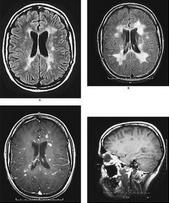

⑤電生理和MRI可發現腦內一些亞臨床病灶;MRI發現腦內白質異常信號。一些脊髓炎性脫髓鞘病變呈“假瘤樣”表現,其MRI表現出輕度占位效應,周圍有輕度水腫,可能有片狀出血信號,容易誤診為脊髓腫瘤。目前內科藥物治療效果不佳。

2.症狀體徵:脫髓鞘性脊髓炎多為急性多發性硬化(MS)脊髓型,臨床表現與感染後脊髓炎相似,但進展較緩慢,病情常在1-3周內達到高峰。前驅感染可不明顯,多為不完全橫貫性損害,表現一或雙側下肢無力或癱瘓,伴麻木感,感覺障礙水平不明顯或有兩個平面,並出現尿便障礙。誘發電位及MRI檢查可能發現CNS其他部位病灶。